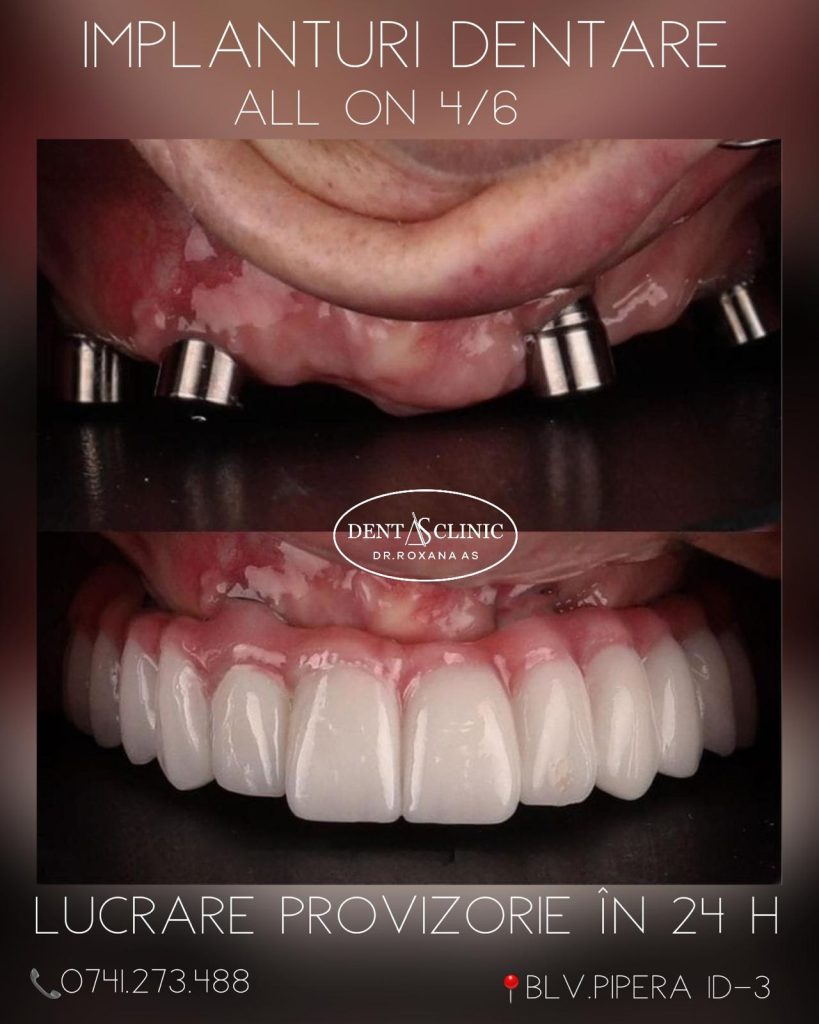

Implantologia este o ramură esențială în medicina dentară, concentrându-se pe restaurarea funcționalității și a esteticii zâmbetului prin intermediul implanturilor dentare. Aceste dispozitive de înaltă tehnologie reprezintă o soluție inovatoare pentru înlocuirea dinților lipsă, restaurând astfel capacitatea de mușcare, încrederea în sine și aspectul natural al zâmbetului dumneavoastră.

Implanturile dentare sunt concepute să funcționeze ca rădăcini artificiale, oferind un suport solid pentru coroanele, puntile sau protezele dentare, indiferent dacă lipsește un singur dinte sau mai mulți

Plasarea implantului dentar reprezintă un proces meticulos și precis, în care punem accent pe fiecare detaliu pentru a asigura succesul intervenției. Utilizăm tehnologii de ultimă generație și materiale de cea mai înaltă calitate pentru a obține rezultate excepționale.

În timpul procedurii de plasare a implantului, echipa noastră de specialiști în implantologie lucrează cu mare atenție pentru a crea un mediu optim pentru integrarea implantului în osul maxilar sau mandibular.

Etapa de restaurare după integrarea implantului în os este esențială pentru a reda pacienților funcționalitatea și aspectul natural al zâmbetului lor. Aceasta implică o abordare personalizată și meticuloasă pentru a crea coroane, punți sau proteze dentare care să se integreze perfect în cadrul zâmbetului.

Coroanele, punțile sau protezele dentare sunt confecționate cu precizie, luând în considerare forma, mărimea și nuanța dinților naturali pentru a asigura o potrivire impecabilă. Echipa noastră de specialiști în implantologie lucrează îndeaproape cu tehnicianul dentar pentru a crea restaurările care să ofere pacienților un zâmbet natural și armonios.